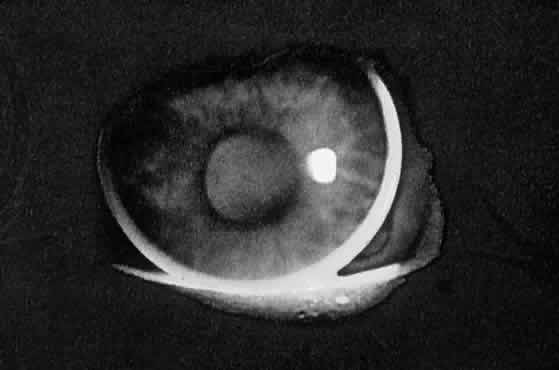

When you look at the lens of an elderly patient through the slit lamp, you

will notice that the reflection from the anterior capsule is blue-white, whereas

the reflection from the posterior capsule is a golden yellow. The

double passage of light through the lens has resulted in a

loss of blue light due to light scattering, producing the yellow reflection. The

more nuclear sclerosis present, the yellower is the reflection. Thus

we can think of the crystalline lens as a minus blue filter, because

of both its yellow pigment and its preferential scattering of

blue light. This concept of the lens as a minus blue filter was suggested by Dr. Aran

Safir2 and helps to explain why the optic nerve looks more yellow in the phakic

eye than in the aphakic eye. In fact, to the medical student, the blue-white

appearance of the optic nerve in the aphakic eye may be confused